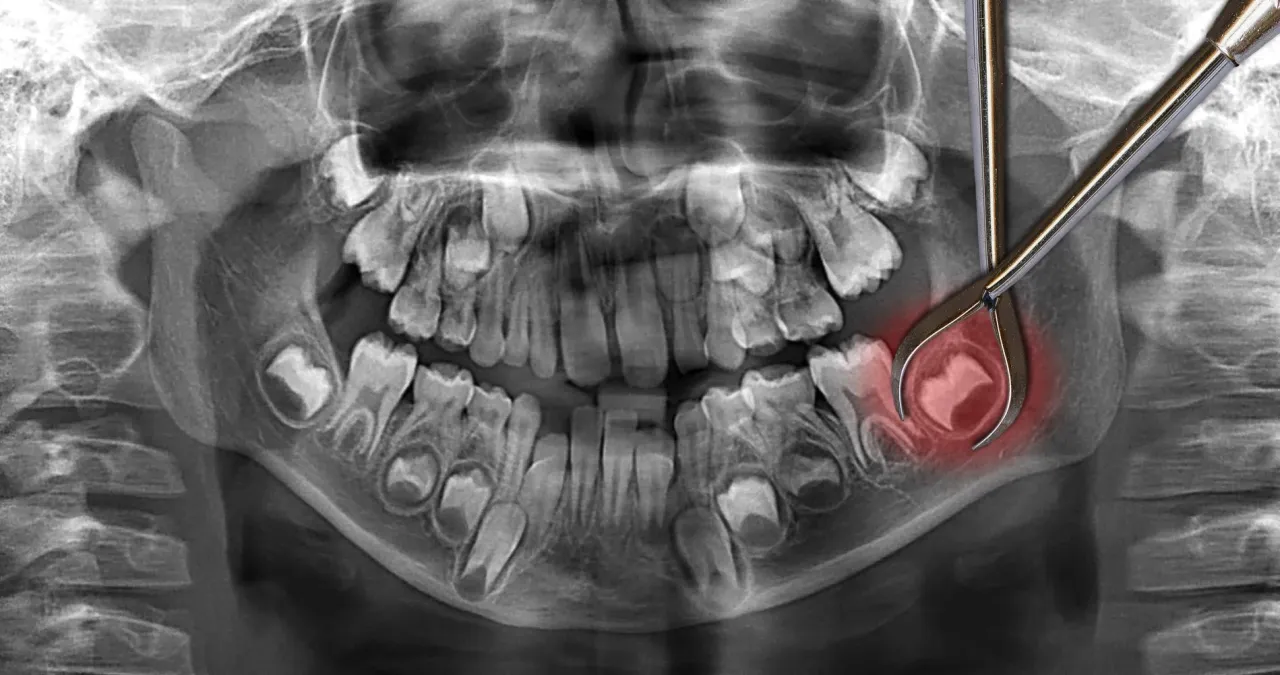

Wyrastanie ósemek, czyli zębów mądrości, może wiązać się z różnymi komplikacjami zdrowotnymi. Wiele osób doświadcza bólu, dyskomfortu oraz innych problemów, które mogą wynikać z niewłaściwego wzrostu tych zębów. Często ósemki mogą być zatrzymane, co oznacza, że nie mają wystarczająco dużo miejsca, aby w pełni się wykształcić. Takie sytuacje mogą prowadzić do stanów zapalnych, infekcji oraz uszkodzenia sąsiadujących zębów.

Inne potencjalne komplikacje obejmują torbiele, które mogą powstawać wokół zatrzymanych zębów, a także ich przemieszczenie, co może wpływać na zgryz. Warto zwrócić uwagę na te problemy, aby uniknąć poważniejszych konsekwencji zdrowotnych i zapewnić prawidłowy rozwój zębów. Regularne kontrole u dentysty są kluczowe dla monitorowania stanu ósemek i wczesnego wykrywania ewentualnych problemów.

W przypadku, gdy zęby mądrości, czyli ósemki, nie wyrastają prawidłowo lub powodują poważne dolegliwości, ich usunięcie może być konieczne. Warto przygotować się na ten proces, aby zminimalizować stres i zapewnić sobie komfort w czasie rekonwalescencji. Przede wszystkim, przed zabiegiem warto skonsultować się z dentystą, który oceni stan zębów i zaproponuje najlepsze rozwiązania. Wiele osób nie zdaje sobie sprawy, że planowanie diety po usunięciu zębów mądrości jest kluczowe; zaleca się spożywanie miękkich pokarmów, takich jak purée ziemniaczane, jogurty czy zupy, aby ułatwić sobie jedzenie w pierwszych dniach po zabiegu.